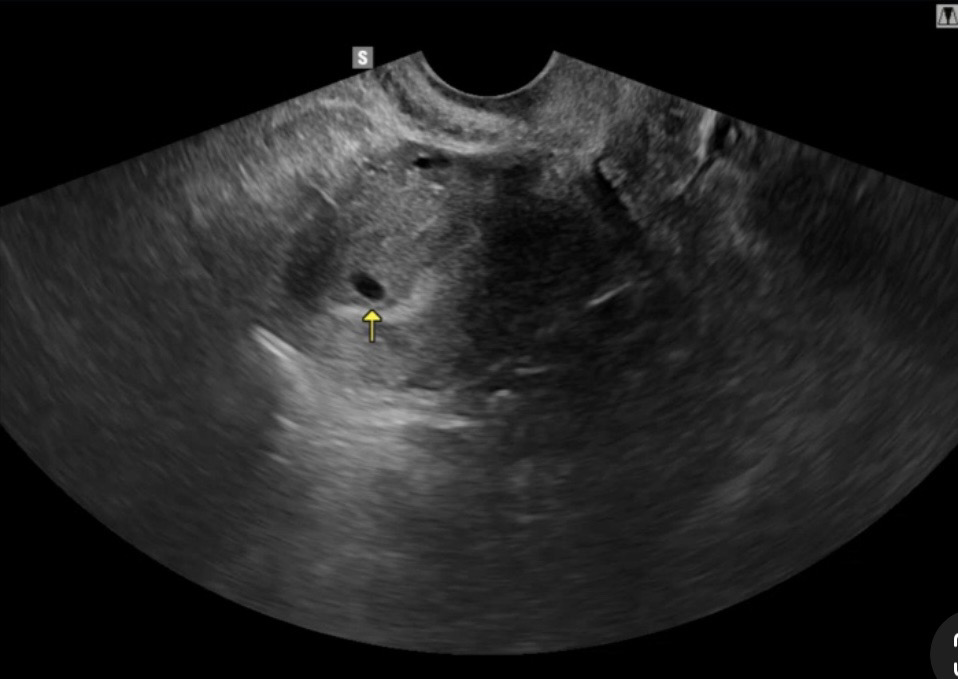

5주0일차 인데 2주뒤에 아기크기보고 변경될수있다고 하시더라구요~~~~~ 간혹 난황까지 보시는 분들 있어서 내심 기대했는데 못봐서 아쉽네요 ㅠㅠㅠ 크기는 0.60mm 이라더라구요~~~ 아직은 난황이 안보이는 시기인거 맞죠? ㅠㅠㅠㅠㅠㅠ 다른 분들은 어떠셨나요 ㅠㅠㅠ 2주뒤에 병원가는데 정말시간이 안갑니다 ㅠㅠㅠ 설렘반 걱정반으로 기다리는 요즘입니다~~